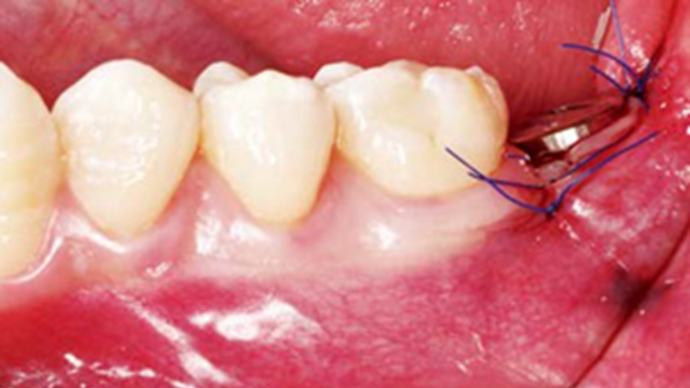

Clinical case: Bone filling into the bottom of deepest thread at 8.0mm AnyRidge fixture

- Courtesy of Dr. Kwang Bum Park -

Keywords

AnyRidge, Knifethread ,extraction socket, ,initial stability ,Allograft, ,osseointegratio ,Dr. Kwang Bum Park, , Mandibular, Single replacement, AnyRidge, Mega-oss,

Products used

Implant system-AnyRidge, Regeneration-Mega-Oss